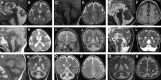

The homologous genes GTPBP1 and GTPBP2 encode GTP-binding proteins 1 and 2, which are involved in ribosomal homeostasis. Pathogenic variants in GTPBP2 were recently shown to be an ultra-rare cause of neurodegenerative or neurodevelopmental disorders (NDDs). Until now, no human phenotype has been linked to GTPBP1. Here, we describe individuals carrying bi-allelic GTPBP1 variants that display an identical phenotype with GTPBP2 and characterize the overall spectrum of GTP-binding protein (1/2)-related disorders. In this study, 20 individuals from 16 families with distinct NDDs and syndromic facial features were investigated by whole-exome (WES) or whole-genome (WGS) sequencing. To assess the functional impact of the identified genetic variants, semi-quantitative PCR, western blot, and ribosome profiling assays were performed in fibroblasts from affected individuals. We also investigated the effect of reducing expression of CG2017, an ortholog of human GTPBP1/2, in the fruit fly Drosophila melanogaster. Individuals with bi-allelic GTPBP1 or GTPBP2 variants presented with microcephaly, profound neurodevelopmental impairment, pathognomonic craniofacial features, and ectodermal defects. Abnormal vision and/or hearing, progressive spasticity, choreoathetoid movements, refractory epilepsy, and brain atrophy were part of the core phenotype of this syndrome. Cell line studies identified a loss-of-function (LoF) impact of the disease-associated variants but no significant abnormalities on ribosome profiling. Reduced expression of CG2017 isoforms was associated with locomotor impairment in Drosophila. In conclusion, bi-allelic GTPBP1 and GTPBP2 LoF variants cause an identical, distinct neurodevelopmental syndrome. Mutant CG2017 knockout flies display motor impairment, highlighting the conserved role for GTP-binding proteins in CNS development across species.